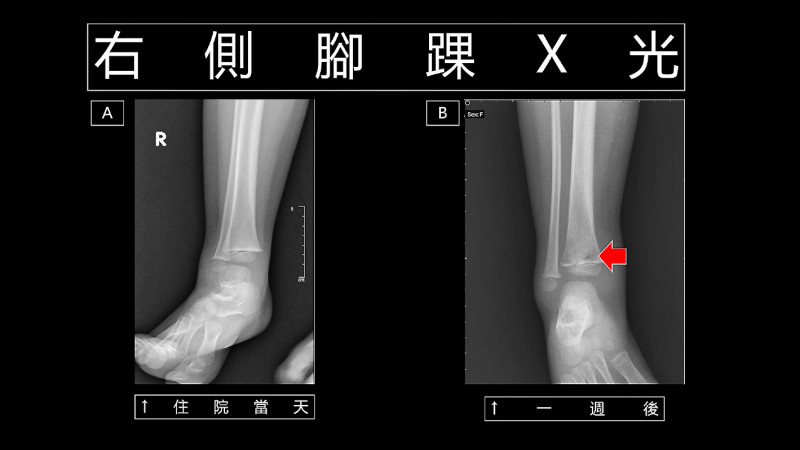

理學檢查結果顯示,她不肯走路的原因是因右側小腿疼痛,但是X光顯示,右側腳踝沒有骨折等明顯異常(圖A)。除此之外,第1次到急診的血液培養出了金黃葡萄球菌,於是父母親決定住院治療。

住院之後,雖然給予適當的抗生素,但還是發燒,右側小腿不但痛,也變得有紅腫現象。X光顯示,右側腳踝遠端脛骨有被侵蝕(圖B),再加上其他檢查確定有骨髓炎伴隨膿瘍生成,因此骨科醫師為她進行清創手術。